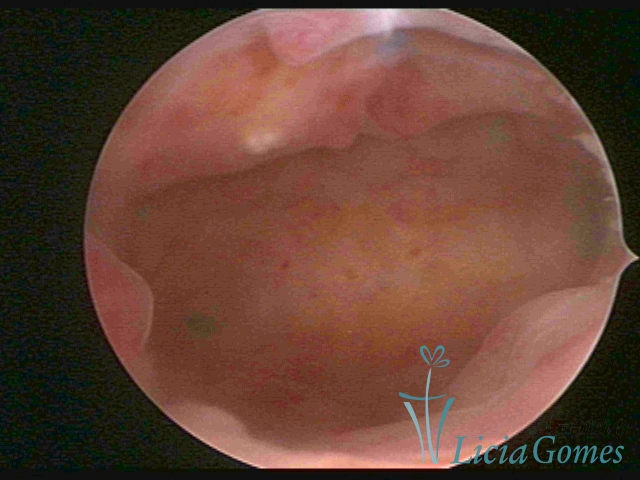

In simple hypertrophy, there is an increase in the endometrial thickness with a protuberance of the glandular punctuate, differing from the proliferative endometrial pattern by the loss of superficial reticular vascularization. Another form of simple hyperplasia is the cystic glandular hyperplasia, which also presents cystic lesions intercalated to the hypertrophic endometrium.